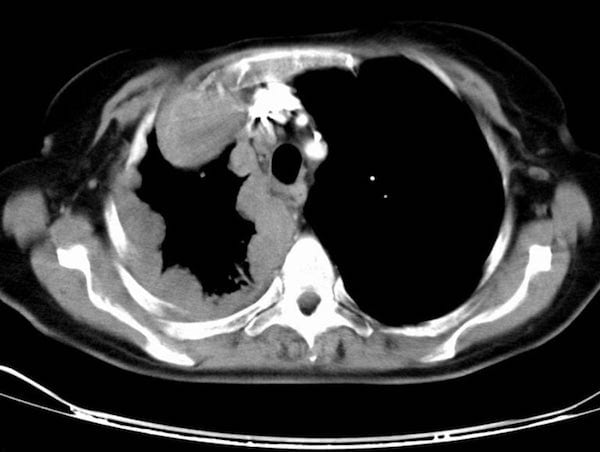

CT Interpretation:

CT chest demonstrates circumferential pleural thickening.